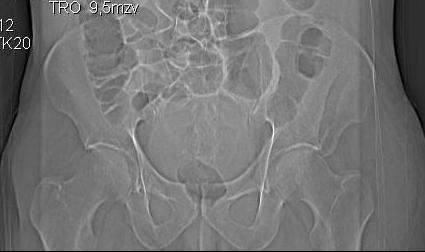

Уважаемые коллеги! Хотелось бы услышать ваше мнение. Мужчина 50л поступил с переломами костей таза. Закрытый перелом крыла подвздошной кости, переднего края вертлужной впадины справа.

Достаточно ли консервативного лечения, стоит ли беспокоиться о переднем крае? В приложении КТ.

По предоставленым снимкам верифицировать повреждение невозможно.

Покажите обзорный снимок таза и проекции Judet.